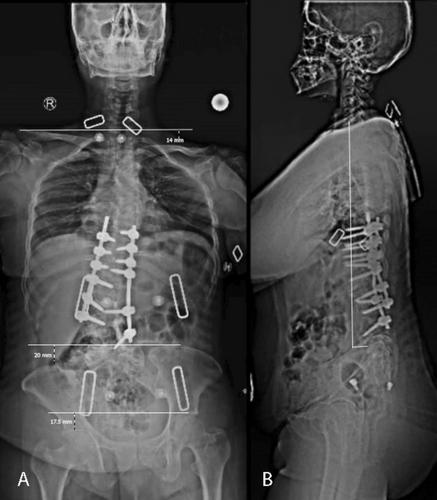

成人复杂的脊柱畸形,通常来自被忽视的先天性畸形,给手术带来了挑战。了解3D解剖结构是至关重要的。3d打印脊柱模型有助于术前计划、术中导航和教育。它减少了手术时间、出血和x线剂量,同时提高了螺钉放置的准确性和脊柱内病变的导航。

Complex spinal deformity in adults, often from neglected congenital deformities, poses surgical challenges. Understanding the 3D anatomy is crucial. A 3D-printed spinal model aids pre-operative planning, intra-operative navigation, and education. It reduces surgery time, bleeding, and X-ray dose, while improving screw placement accuracy and navigation of intra-spinal pathologies.